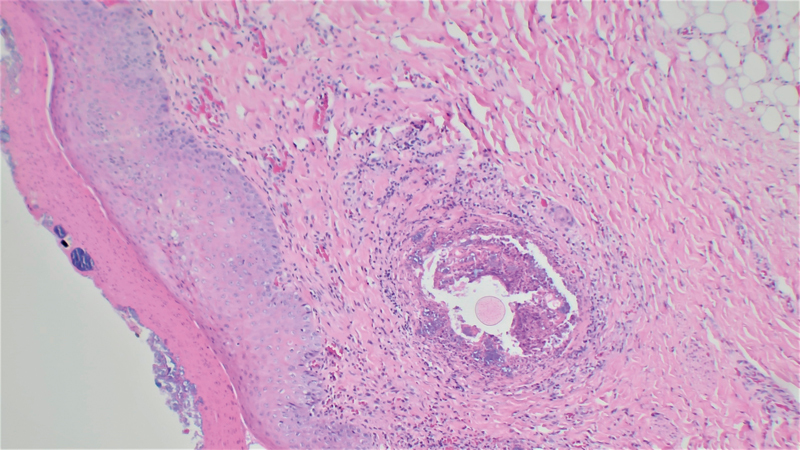

A massive outbreak of exudative epidermitis (EE) occurred on a Western German piglet producing farm with 350 productive sows. Gilts are produced on site. In one group of piglets, more than 50% of suckling and nursery piglets were clinically affected; furthermore, gilts as well as sows showed localized blackish-squamous skin lesions in the neck area. Generalized infection in suckling and nursery piglets resulted in mortality rates of up to 10% per weaning group. Swabs of moist, affected areas of skin taken on the farm in addition to swab and organ samples collected during necropsy were examined via bacterial cultivation. Both Staphylococcus (St.) hyicus and St. chromogenes strains were detected in affected skin lesions, with St. hyicus also present in systemic localizations. Further characterization of the St. hyicus strains identified ExhA and SHETA as toxins involved, and isolates showed resistance to penicillin and aminopenicillin. In the short term, antibiotic treatment with trimethoprim-sulfadiazine of the whole age group combined with individual treatment of severely affected animals as well as washing with an iodine-containing solution improved the clinical signs. In order to reduce the antibiotic use, an autogenous vaccine against the isolated St. hyicus and St. chromogenes strains for gilts and sows was produced and applied as a basic immunization twice before farrowing. In addition, external and internal biosecurity was evaluated and adjusted using an objective questionnaire (Bio-check.UGentTM). The combination of taken measures resulted in a long-term improvement of the overall health status. Several months after the severe EE outbreak, the sporadic occurrence of new EE cases in individual piglets could be controlled by the adjustment of the autogenous vaccine with an additional St. hyicus isolate. The case report illustrates how the combination of continuous monitoring, individual and group antibiotic treatment, biosecurity evaluation, and the use of appropriate immune prophylaxis can improve the clinical picture of EE.

Abstract Image